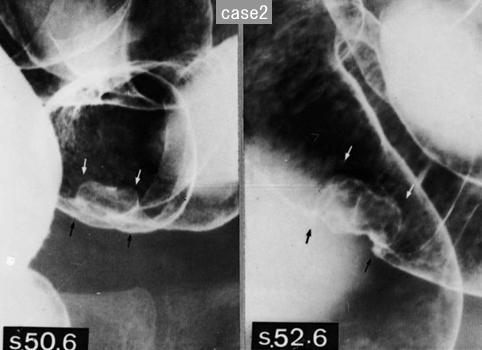

Posted by: Tokyo Pref., Centro Nacional de curaciones de Cáncer, Hospital Central y Centro Kyusyu de Curaciones de Cáncerc

ID:12221

[Image-ID:12221]